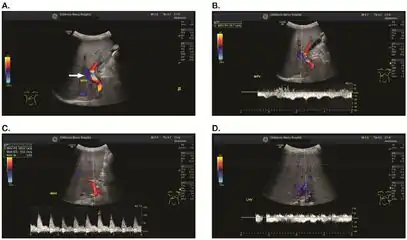

Doppler ultrasound of the liver is typically utilized to confirm or suggest the diagnosis. Common findings on liver doppler ultrasound include increased phasicity of portal veins with eventual development of portal flow reversal. The liver is usually enlarged but maintained normal echogenicity. A liver biopsy is required for a definitive diagnosis.